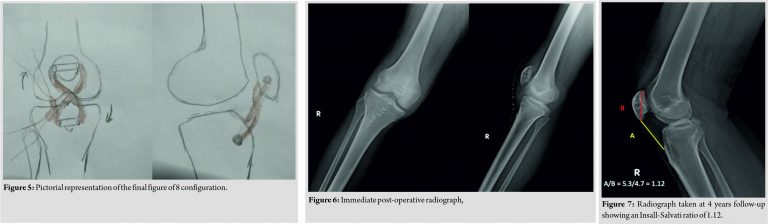

This gave the final structure a figure of 8 configurations (Fig. 5). The stability of the reconstructed tendon was checked under flexion and extension. Patella slid inferiorly during flexion and superiorly during extension. No extensor lag or maltracking was noted. Knee was maintained in extension for 2 weeks with an above-knee slab (Fig. 6). Sutures were removed after 2 weeks. The slab was converted into the cast and maintained for 4 weeks in extension. After 4 weeks, the patient was started on gentle knee mobilization along with quadriceps and hamstring strengthening exercises. The patient had no extensor lag, and he was walking full-weight-bearing with a normal gait at 4 months after surgery. At 3 years follow-up, the patient had full range of painless motion with no signs of infection or activity limitation with normalized Insall-Salvati ratio (Fig. 7).

The patient was positioned supine with spinal anesthesia. Tourniquet was avoided as it would have hindered with intraoperative patellar length assessment due to quadriceps tethering. A vertical midline incision was taken from the center of the patella to tibial tuberosity. Patellar tendon was found to be lacerated and retracted. Adhesions around the patella and quadriceps tendon were released. Tendoachilles’ allograft of length 23 cm was procured from a tissue bank adhering to strict protocols. The graft was acquired 1 h before the surgery after informing the previous day. It was thawed, then cleaned with normal saline and 5% povidone-iodine solution. Distal bony attachment was excised. The graft was cut along its length to give a thickness of 5 mm. A tunnel was created in patella and tibial tuberosity with a 5 mm reamer (Fig. 3). One end of the graft was stitched with polyethylene terephthalate 2–0 and anchored on a Beath pin. The pin with the graft was first passed from lateral to the medial side of the tibial tuberosity and then from lateral to medial end of the patella, the ends of which were sutured with a thick non-absorbable suture. We noted the tendon to be in the excess length of 1.5 cm which was resected. Suturing and tightening were done with knee in extension. The knot was formed on the lateral side of the tibial end (Fig. 4).